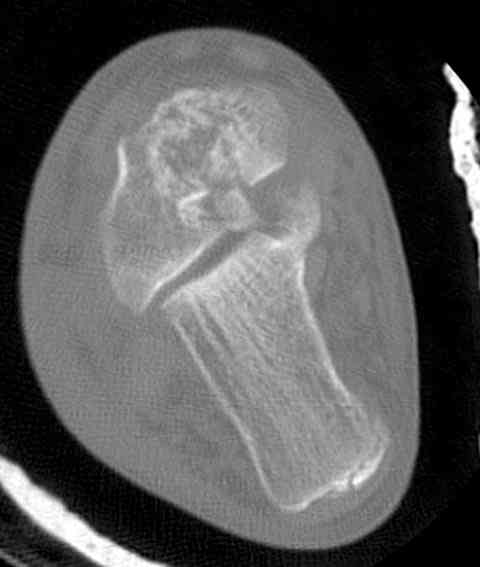

Случай с множественным оскольчатым переломом тарана оперированный из двойного доступа.

Через 8 мес.: